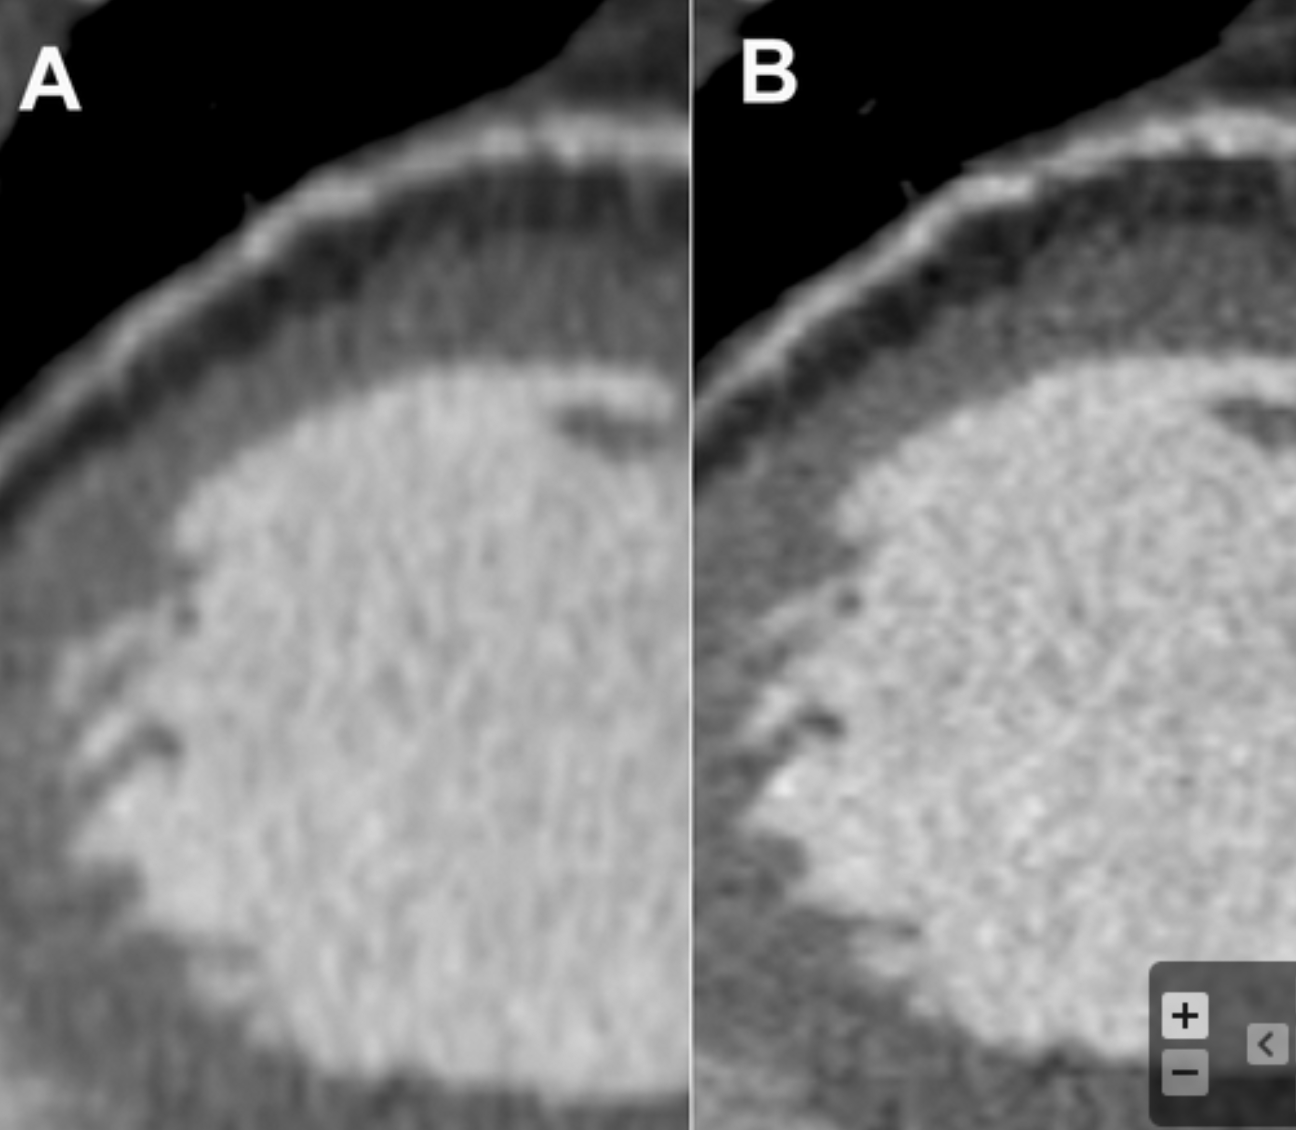

Describe the findings and technique used to improve the quality of the image